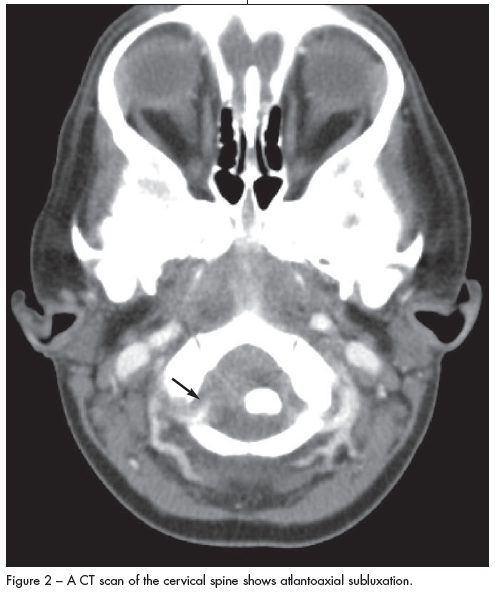

A lateral cervical spine radiograph showed subluxation (Figure 1). CT scans with contrast revealed marked anterior subluxation of C1 on C2 measuring 1 cm (Figure 2). Thickening of the retropharyngeal soft tissues with an unchanged area of phlegmon was also noted. These findings were confirmed by MRI. The patient was immediately placed in a cervical collar for pain relief, and a neurosurgical consultation was obtained.

The diagnosis was Grisel syndrome— atlantoaxial rotatory subluxation secondary to the retropharyngeal phlegmon.